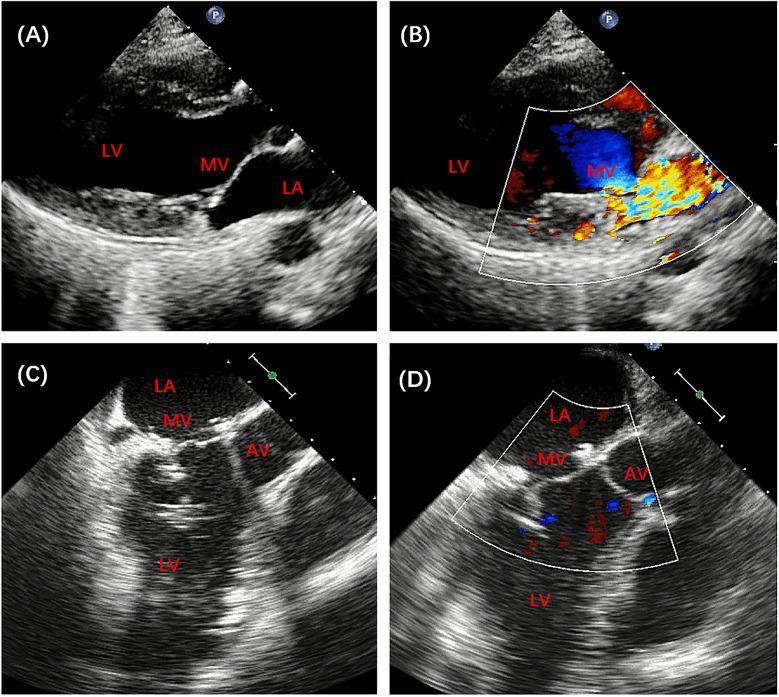

Case Report: Surgical repair of mitral prolapse caused by papillary muscle elongation using premeasured artificial chordae: a case series.

Artificial chordae are increasingly used to repair mitral prolapse. The application of premeasured artificial chordae facilitates the creation of chordae with an appropriate length. Herein, we describe our experience of applying premeasured artificial chordae in 14 cases of mitral prolapse caused by elongated papillary muscles, with an emphasis on the importance of restoring the physiological features of sub-valvular structures during mitral valve repair.